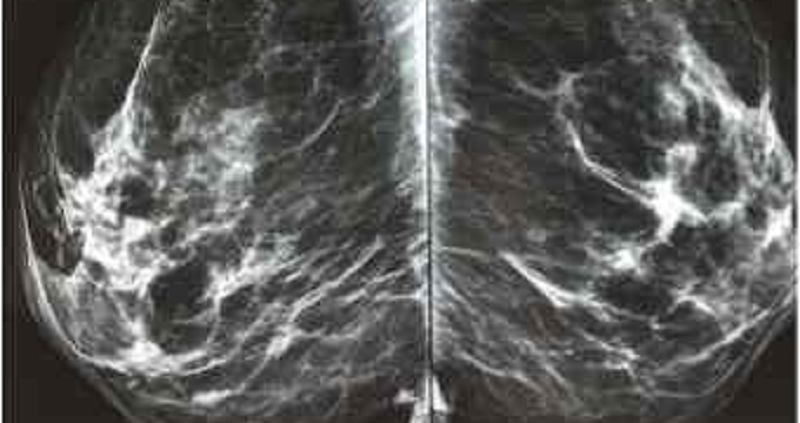

{"name":"Quiz Biofísica - Daniel Malta - 119", "url":"https://www.quiz-maker.com/QPREVIEW","txt":"1. Analise as situações a seguir e assinale a alternativa correta. I. Em agosto de 1987, Mateus recebeu uma proposta de trabalho em Goiânia, capital do estado de Goiás. Depois de um mês conseguiu se adaptar e fez amigos na região, até que um dia, Gabriel, seu amigo, chegou em sua casa com uma pequena cápsula azul brilhante e a entregou de presente para Mateus, que pegou a cápsula e a colocou na sua mesa de cabeceira ao lado da cama. O que eles não sabiam é que esse material era o Césio-137, uma substância radioativa altamente perigosa. II. Gabrielle é uma técnica de radiologia que trabalha meio período no maior hospital da cidade em que mora. Por ser um hospital de referência, Gabrielle tem uma alta demanda todos os dias e realiza inúmeros exames que envolvem a emissão de raios X para diagnósticos de imagem. III. Millena fez a feira do mês recentemente e comprou uma quantidade significativa de frutas e verduras. Suas refeições normalmente apresentam um protagonismo forte desses alimentos. Depois de uma semana Millena viu na televisão que a indústria alimentícia utilizava da radiação proveniente do Césio-137 e do Cobalto-60 para esterilizar alimentos e descobriu que esse foi o método usado nas frutas que ela tem ingerido., 2. Igor chegou ao ambulatório sentindo fortes náuseas e relatou alguns episódios de vômitos. O médico clínico geral tratou esses sintomas e orientou o paciente para que observasse como seria o decorrer dos próximos dias. Após 3 dias o mesmo paciente retorna com diarreia, dores de cabeça, febre. O médico achou estranho e pediu para que Igor descrevesse seus últimos dias detalhadamente. Qual o possível diagnóstico dado pelo médico?, 3. Um técnico de radiologia estava acompanhando sua última paciente do dia durante uma mamografia de rotina. Como estava apressado para terminar logo o expediente, não orientou corretamente a paciente em relação às medidas de radioproteção e ela não fez uso da vestimenta plumbífera. Em relação à situação apresentada anteriormente, assinale a alternativa correta quanto aos princípios de radioproteção.","img":"https://www.quiz-maker.com/3012/CDN/84-4053312/mamografia.jpg?sz=1200-00000019641000005300"}